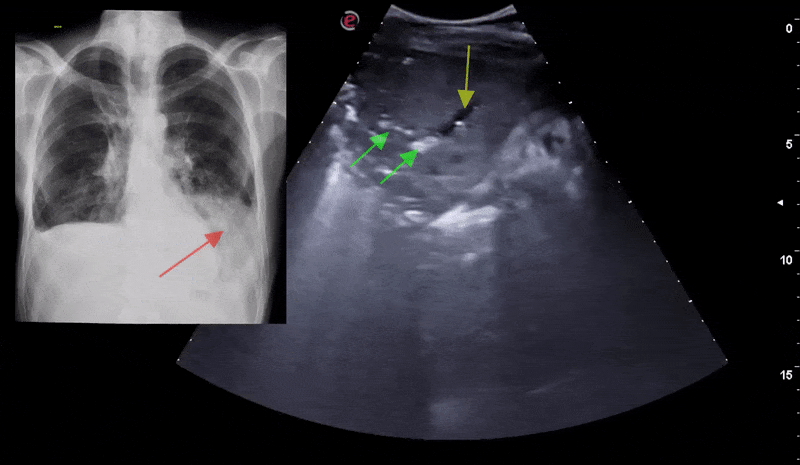

Chest X-ray images (anterior-posterior) were selected from retrospective cohorts of pediatric patients of one to five years old from Guangzhou Women and Children’s Medical Center, Guangzhou. All chest X-ray imaging was performed as part of patients’ routine clinical care.

For the analysis of chest x-ray images, all chest radiographs were initially screened for quality control by removing all low quality or unreadable scans. The diagnoses for the images were then graded by two expert physicians before being cleared for training the AI system. In order to account for any grading errors, the evaluation set was also checked by a third expert.